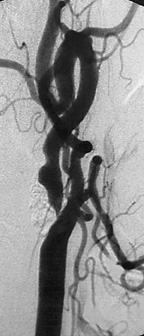

The carotid arteries are the two large blood vessels at each side of the neck. When the arteries become narrow or blocked, the lack of blood flow and oxygen to the brain can cause a stroke. Harlan had blockage in both carotid arteries (nearly 90 percent on one artery and 80 percent on the other artery), and ended up having two stents (wire mesh tubes) inserted — one in each artery — within two months. The stents help to keep the blocked arteries open in much the same way as a balloon is used in angioplasty to open a blocked coronary artery.

Traditional surgery would have involved an incision into the neck to open the carotid artery, as well as a longer in-hospital stay and recovery time. Instead, Dr. Mortazavi inserted a tiny catheter with a collapsed stent (a fine, tubular wire mesh) through a small incision in the groin. Using X-ray imaging, he then guided the catheter up to the blockage in the neck and inflated the stent to restore normal blood flow.

Carotid Artery Blockage & Stents

Carotid artery stenosis – or blockage — occurs when the carotid arteries narrow, usually due to the buildup of fatty materials under the inner lining of the arterial wall. The blockage can cause a sudden loss of brain function (stroke). The risk of stroke increases with the degree of blockage. Generally, surgery is recommended if the blockage is more than 70 percent.

With minimally invasive procedures, there is no incision in the neck or the artery. Instead, the collapsed stent is inserted through a small incision in the leg. Benefits include a shorter hospital stay (within 24 hours), faster recovery, and no large incision or scar.

For years, the only way to repair a blockage in one or both of the carotid arteries was traditional open surgery involving a large incision in the neck. With the new, minimally invasive procedure, the stent is inserted endovascularly (within the blood vessel) through a small opening in the groin.

This less invasive procedure benefits patients with serious medical conditions who are at higher risk for surgery. The physician inserts a fine wire, which travels inside the catheter, and guides it to a point beyond the lesion (blockage). The wire has an umbrella-like filtration tip that provides protection from floating debris. Once the filtration device is in place, the stent is expanded. The stent holds the artery open, restoring the blood supply and helping to prevent the risk of stroke in the future.